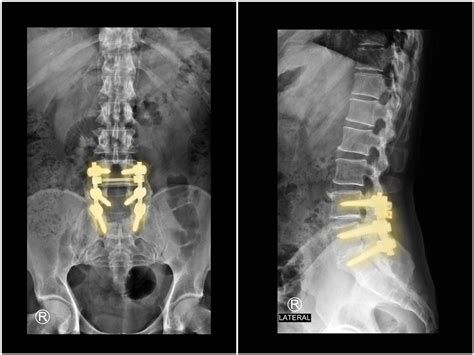

- 수술적 치료(예: 디스크 절제술, 협착 부위 감압술, 유합술 등)는 신경 압박을 직접적으로 해소하여 빠른 증상 개선이 가능합니다.